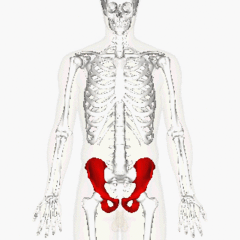

pelv/o

Front

pelvis

Back